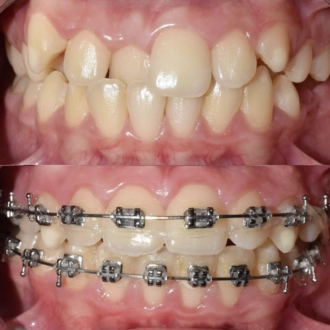

Результат коррекции металлической брекет-системой

Результат коррекции самолигирующей брекет-системой

Результат коррекции керамической брекет-системой